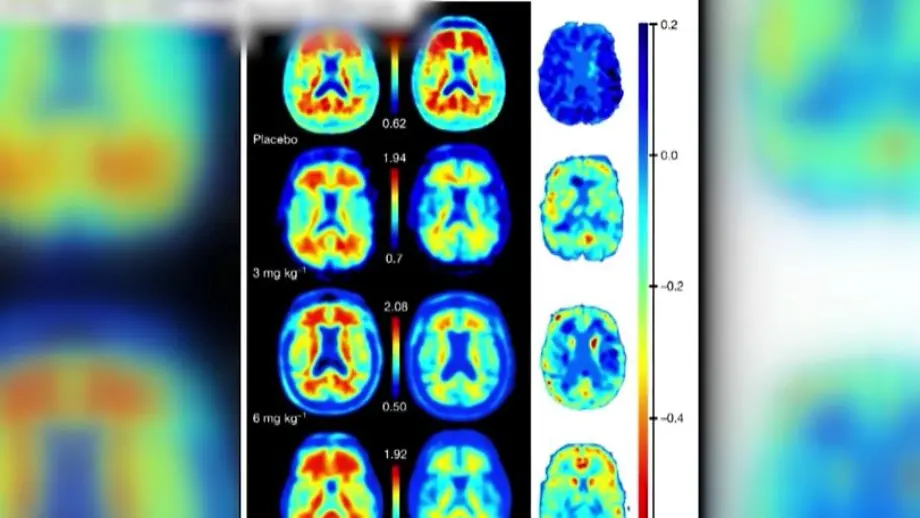

Die Behörde betont in ihrer Stellungnahme, dass es zwingend Maßnahmen zur Risikominimierung geben müsse. Vor Beginn der Behandlung und vor der 5., 7. und 14. Lecanemab -Dosis müssen bei den Patienten demnach MRT-Scans durchgeführt werden, zusätzliche Scans bei Warnzeichen wie Kopfschmerzen, Sehstörungen und Schwindel.